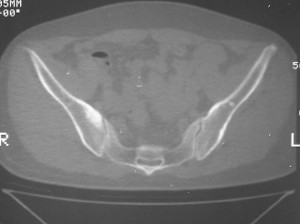

标题: CT7246: F,30岁,下腰痛,同事的片子,请老师们看看,初 [打印本页]

标题: CT7246: F,30岁,下腰痛,同事的片子,请老师们看看,初

典型的致密性髂骨炎

典型的双侧骶髂关节致密性骨炎.

支持,致密性骨炎。经产妇占绝大多数,站立工作人员发病较高!

致密的骨质可以逐渐消失而趋于正常!

致密性骨炎,好发于骶髂关节的髂骨侧的耳状面(少见部位有骶骨,耻骨联合,甚至锁骨也有报道),好发于育龄期的妇女,多对称发病

何谓髂骨致密性骨炎?髂骨致密性骨炎是发生于髂骨耳状关节部分的骨质密度增高性疾病。病因迄今不明,可能与妊娠、机械性劳损、病灶性炎症有关。本病好发于20~35岁的育龄妇女,偶见男性。

髂骨致密性骨炎的临床表现与体征:腰骶部疼痛,多呈慢性、间歇性酸痛、隐痛,可向一侧或双侧臀部及大腿后侧扩散,但不沿坐骨神经方向放射,步行、站立、负重及劳累后加重,咳嗽、打喷嚏不能使疼痛明显加重,休息后症状减轻。患者腰骶角加大,局部有压痛和肌紧张,骨盆分离和挤压试验阳性,“4”字试验阳性,化验检查多在正常范围内。x线检查,骶髂关节间隙整齐清晰,靠近骶髂关节面中的髂骨耳状关节部分骨质密度增高,呈均匀浓白边缘清晰的骨质致密带,骨小梁消失,无骨质破坏。本病应注意与早期强直性脊柱炎、骶髂关节结核相鉴别。